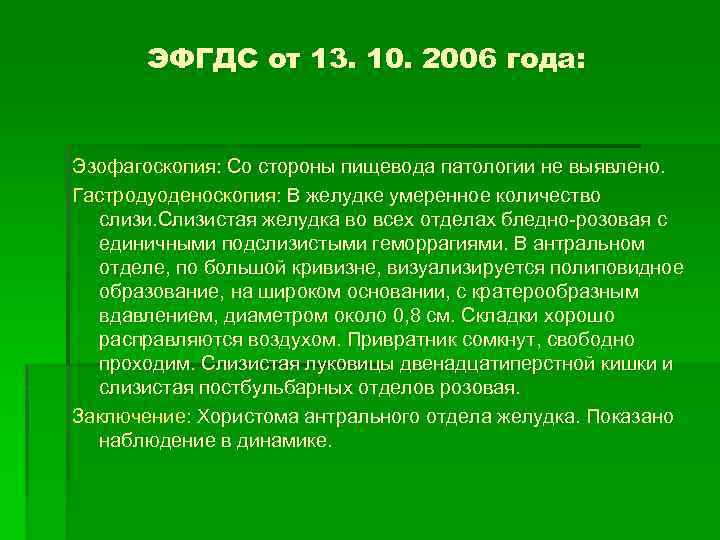

ЭФГДС от 13. 10. 2006 года: Эзофагоскопия: Со стороны пищевода патологии не выявлено. Гастродуоденоскопия: В желудке умеренное количество слизи. Слизистая желудка во всех отделах бледно-розовая с единичными подслизистыми геморрагиями. В антральном отделе, по большой кривизне, визуализируется полиповидное образование, на широком основании, с кратерообразным вдавлением, диаметром около 0, 8 см. Складки хорошо расправляются воздухом. Привратник сомкнут, свободно проходим. Слизистая луковицы двенадцатиперстной кишки и слизистая постбульбарных отделов розовая. Заключение: Хористома антрального отдела желудка. Показано наблюдение в динамике.